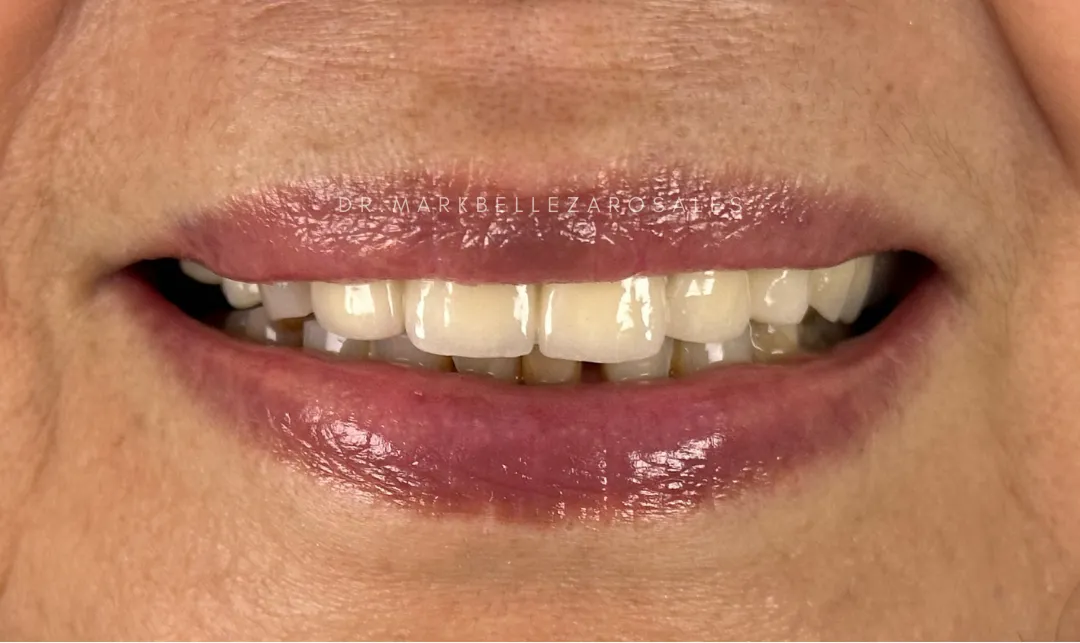

Porcelain bridges are dental restorations used to replace one or more missing teeth by filling the gap with tooth-colored artificial teeth supported by nearby natural teeth. They are designed to look natural, restore proper chewing and speech, and blend smoothly with your existing smile.